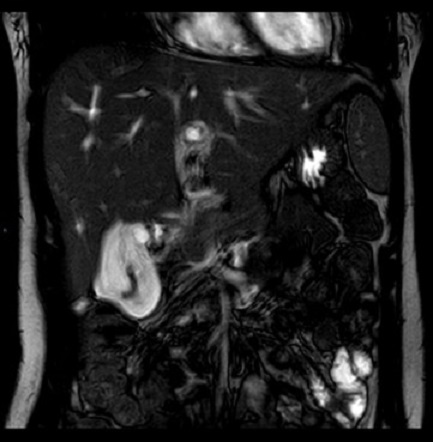

Image de ỈRM de hepatite :

| |

Sur T2 :

Image hypẻrsignal de la region periportale

( oedeme de la region peri portale )et hypersignal legere de parenchyme du foie

|

Sur T1 C+ : Image hyposignal

de la region periportale |

En phase / Op phase : se presence

dans les cas ce qui avait steatose du foie |

Hepatite aigue : Aspect hypersignal de la region periportal .

Hypersignal et epaissisement de la paroi de vesicule billiaire . Image radiologique ỈRM

ponderation sur

T2 de hepatite

viral en coupe axiale . |

Même cas en coupe a travers

tronc portale |